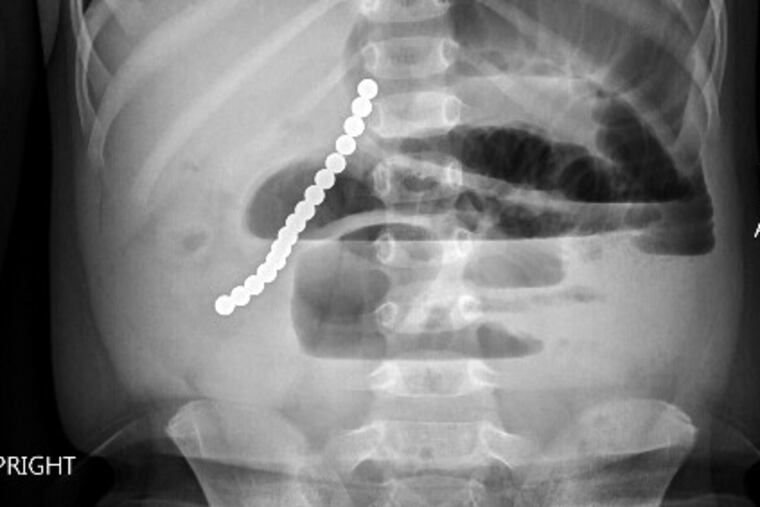

Three nights later, her son was in a hospital, complaining of stomach pains. An X-ray revealed he'd swallowed two magnetic balls. Surgeons removed one. Rather than make a second incision in his intestines, they decided to monitor the boy. He had frequent X-rays until the magnet passed two months later.